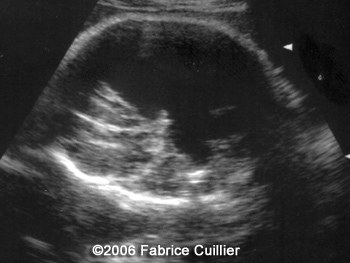

The following images are obtained in a 3rd trimester fetus:

The final diagnosis was: Arachnoid cyst